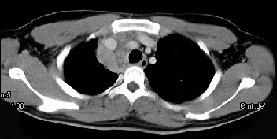

- 女,64岁, 胸背疼痛一周,CT检查如图